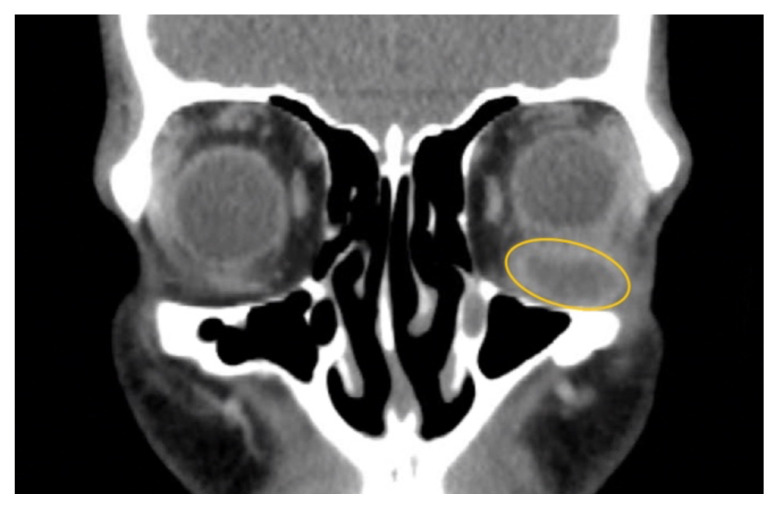

软组织感染,包括脓肿,是急诊科经常遇到的。然而,下直肌脓肿是罕见的,可能会提出独特的诊断和治疗挑战,由于缺乏文献病例。本病例报告强调了一名47岁男性,因急性耐甲氧西林金黄色葡萄球菌感染而出现左下直肌脓肿的治疗。影像显示明显的积液压迫左眼球,引起眼球运动受限和其他症状。尽管先前静脉注射抗生素,脓肿仍然存在。虽然静脉注射抗生素是治疗的重要组成部分,但本病例强调了单独使用这种方法的潜在不足,强调需要手术干预,如眼窝切开引流。本报告补充了关于下直肌脓肿的有限文献,并强调了进一步研究和临床关注以优化患者预后的必要性。主题:脓肿、软组织感染、眼外肌、化脓炎、耐甲氧西林金黄色葡萄球菌、眼球突出、复视、视力丧失。

Soft tissue infections, including abscesses, are frequently encountered in the emergency department. However, abscesses of the inferior rectus muscle are rare and may present unique diagnostic and therapeutic challenges due to the scarcity of documented cases. This case report highlights the treatment of a 47-year-old male presenting with an abscess in the left inferior rectus muscle due to an acute Methicillin-resistant Staphylococcus aureus infection. Imaging revealed a distinct fluid collection compressing the left globe, causing restricted ocular motility and other symptoms. Despite prior intravenous antibiotics, the abscess persisted. While intravenous antibiotics are an important component of treatment, this case highlights the potential insufficiency of this approach alone, emphasizing a need for surgical intervention such as orbitotomy for drainage. This report contributes to the limited literature on inferior rectus muscle abscesses and underscores the need for further research and clinical attention to optimize patient outcomes.